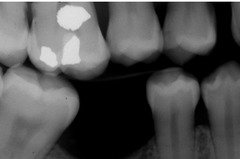

Rampent caries

Front

Back